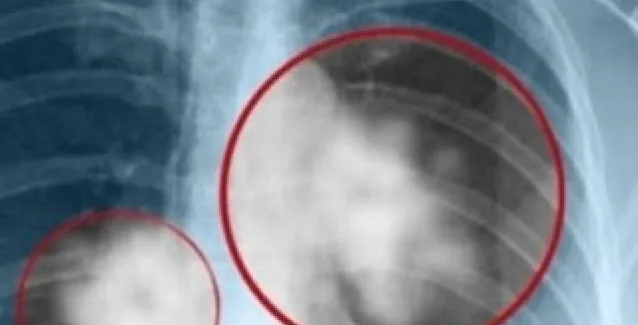

Στο Κέντρο Μοριακής Ανοσολογίας (CIM) στην Κούβα διατίθεται δωρεάν, το πρώτο εμβόλιο στους ασθενείς με καρκίνο του πνεύμονα. Σύμφωνα με τους ειδικούς είναι μια νέα θεραπεία, μοναδική στον κόσμο, η οποία μπορεί να σταματήσει την εξέλιξη της νόσου, χωρίς να επηρεάζει την ποιότητα ζωής των ανθρώπων.

«Τα αποτελέσματα του εμβολίου δίνουν ένα ποσοστό επιβίωσης των ασθενών, ο όγκος δεν εξαλείφεται, αλλά σταματά να αναπτύσσεται, επιτρέποντας στους ασθενείς να ζουν περισσότερο και ιδιαίτερα με μια καλή ποιότητα ζωής, οι παρενέργειες είναι ελάχιστες», λέει η γιατρός Arlhee Diaz.

Το εμβόλιο θα μπορούσε να διατεθεί και σε άλλες χώρες αλλά λόγω του αποκλεισμού από τις ΗΠΑ προς το παρόν είναι ανέφικτο. Το μόνο που μπορεί να επιτευχθεί είναι η εγγραφή σε μια βάση δεδομένων ώστε να γίνει ανταλλαγή απόψεων για την θεραπεία της νόσου. Οι Κουβανοί έχουν πρόσβαση μέσω του εθνικού συστήματος υγείας της χώρας τους ενώ οι αλλοδαποί πληρώνοντας ένα συμβολικό πόσο.